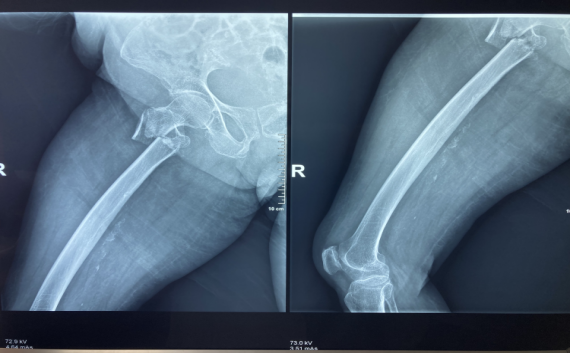

蔡奶奶今年98岁高寿,因“跌伤致右髋部疼痛伴活动受限5天。”到我院骨伤科治疗。入院后,被诊断为“右侧股骨粗隆间骨折”。

“虽然骨折手术并不复杂,但是蔡奶奶属于超高龄患者,各器官功能退化,心、肺功能下降,尤其是对手术的承受力下降、麻醉耐受力的降低、术后感染、康复及一系列并发症,每一道都是难关。”副院长张有文详细介绍,如果保守治疗,蔡奶奶需长期卧床,也容易引发肺部感染、褥疮、深静脉血栓等一系列的并发症,严重可导致生命危险。

术中,麻醉科医生严格控制麻醉药品的剂量和浓度,密切观察病情,监测各项生理指标,确保老人的生命体征平稳。副院长张有文为百岁老人实施了右股骨粗隆间骨折闭合复位髓内钉内固定术,历时40分钟,手术圆满完成。